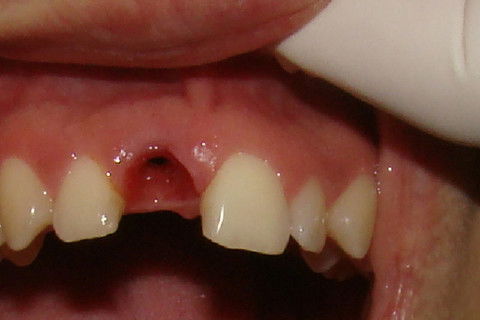

Foto frontal da paciente antes da reabertura

Vista da depressão gingival vestibular na região do implante a ser reaberto

Paciente com implante feito em curso de atualização, chega ao consultório para reabertura e coroa metalo-ceramica unitária, com grande depressão gengival na vestibular do elemento 11. Feita a reabertura com concomitante enxerto de tecido conjuntivo para otimizar os tecidos moles, aguardamos 3 semanas para inicio das moldagens para a coroa temporária. Após colocação e ajustes da coroa temporária parafusada, aguardamos 3 meses para completa maturação dos tecidos e então fizemos nova moldagem, com personalização do transferente para moldeira aberta individual e fizemos coros metalo-cerâmica parafusada.